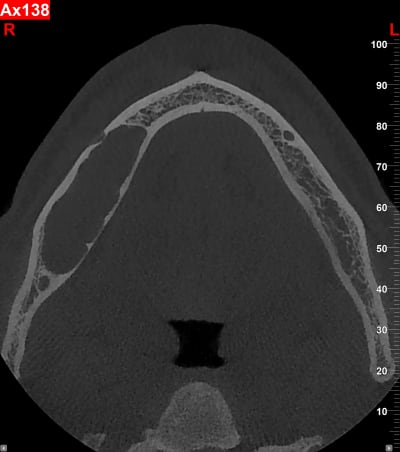

J'en ai déjà eu 3 comme ça, originaires de pays de l'est voir de l’extrême-est.

Un père pour un trou de 48 à 36 et son fils autour d'une 43 incluse. (origine génétique ?)

Et un autre au niveau latéral doit.

Idem adressé au CHU le plus proche.

Bon je sais , ça fait un peu le concours de celui qui à le plus gros ... kyste !!

Qui dit mieux ?